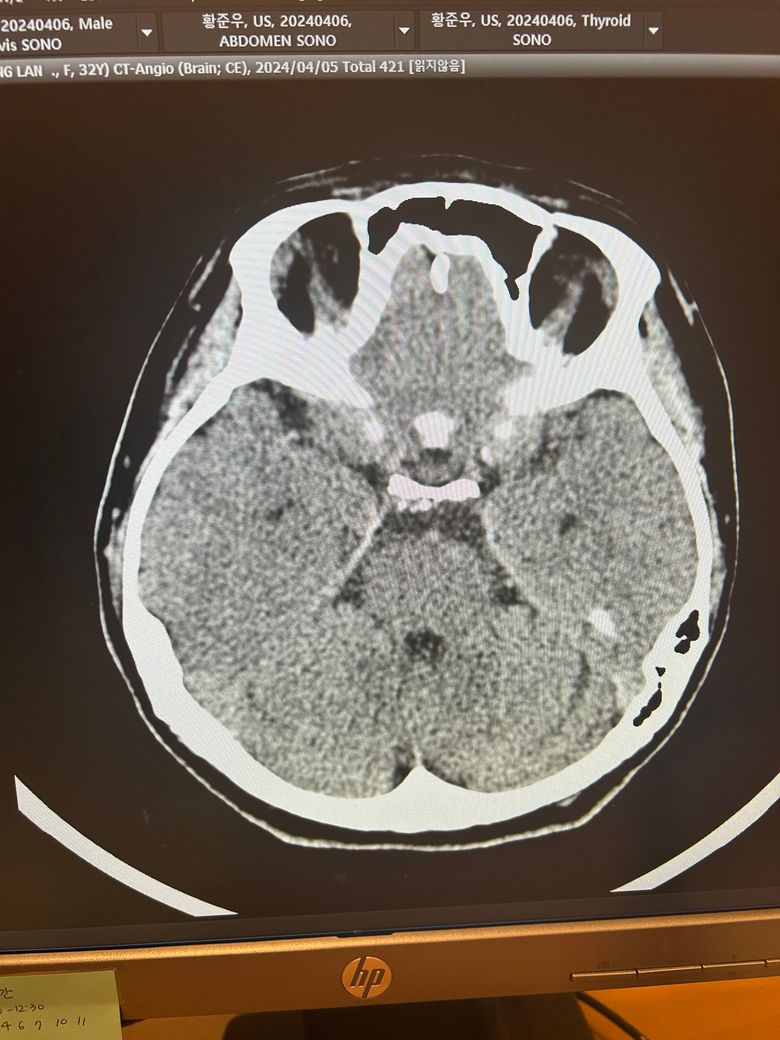

두통과 목뻐근함이 일주일째 심해서 뇌ct검사를 했습니다.

영상은 이렇게 보이는데 어떻게 의심되시나요?

석회화랑 다른것도 보이시나요?